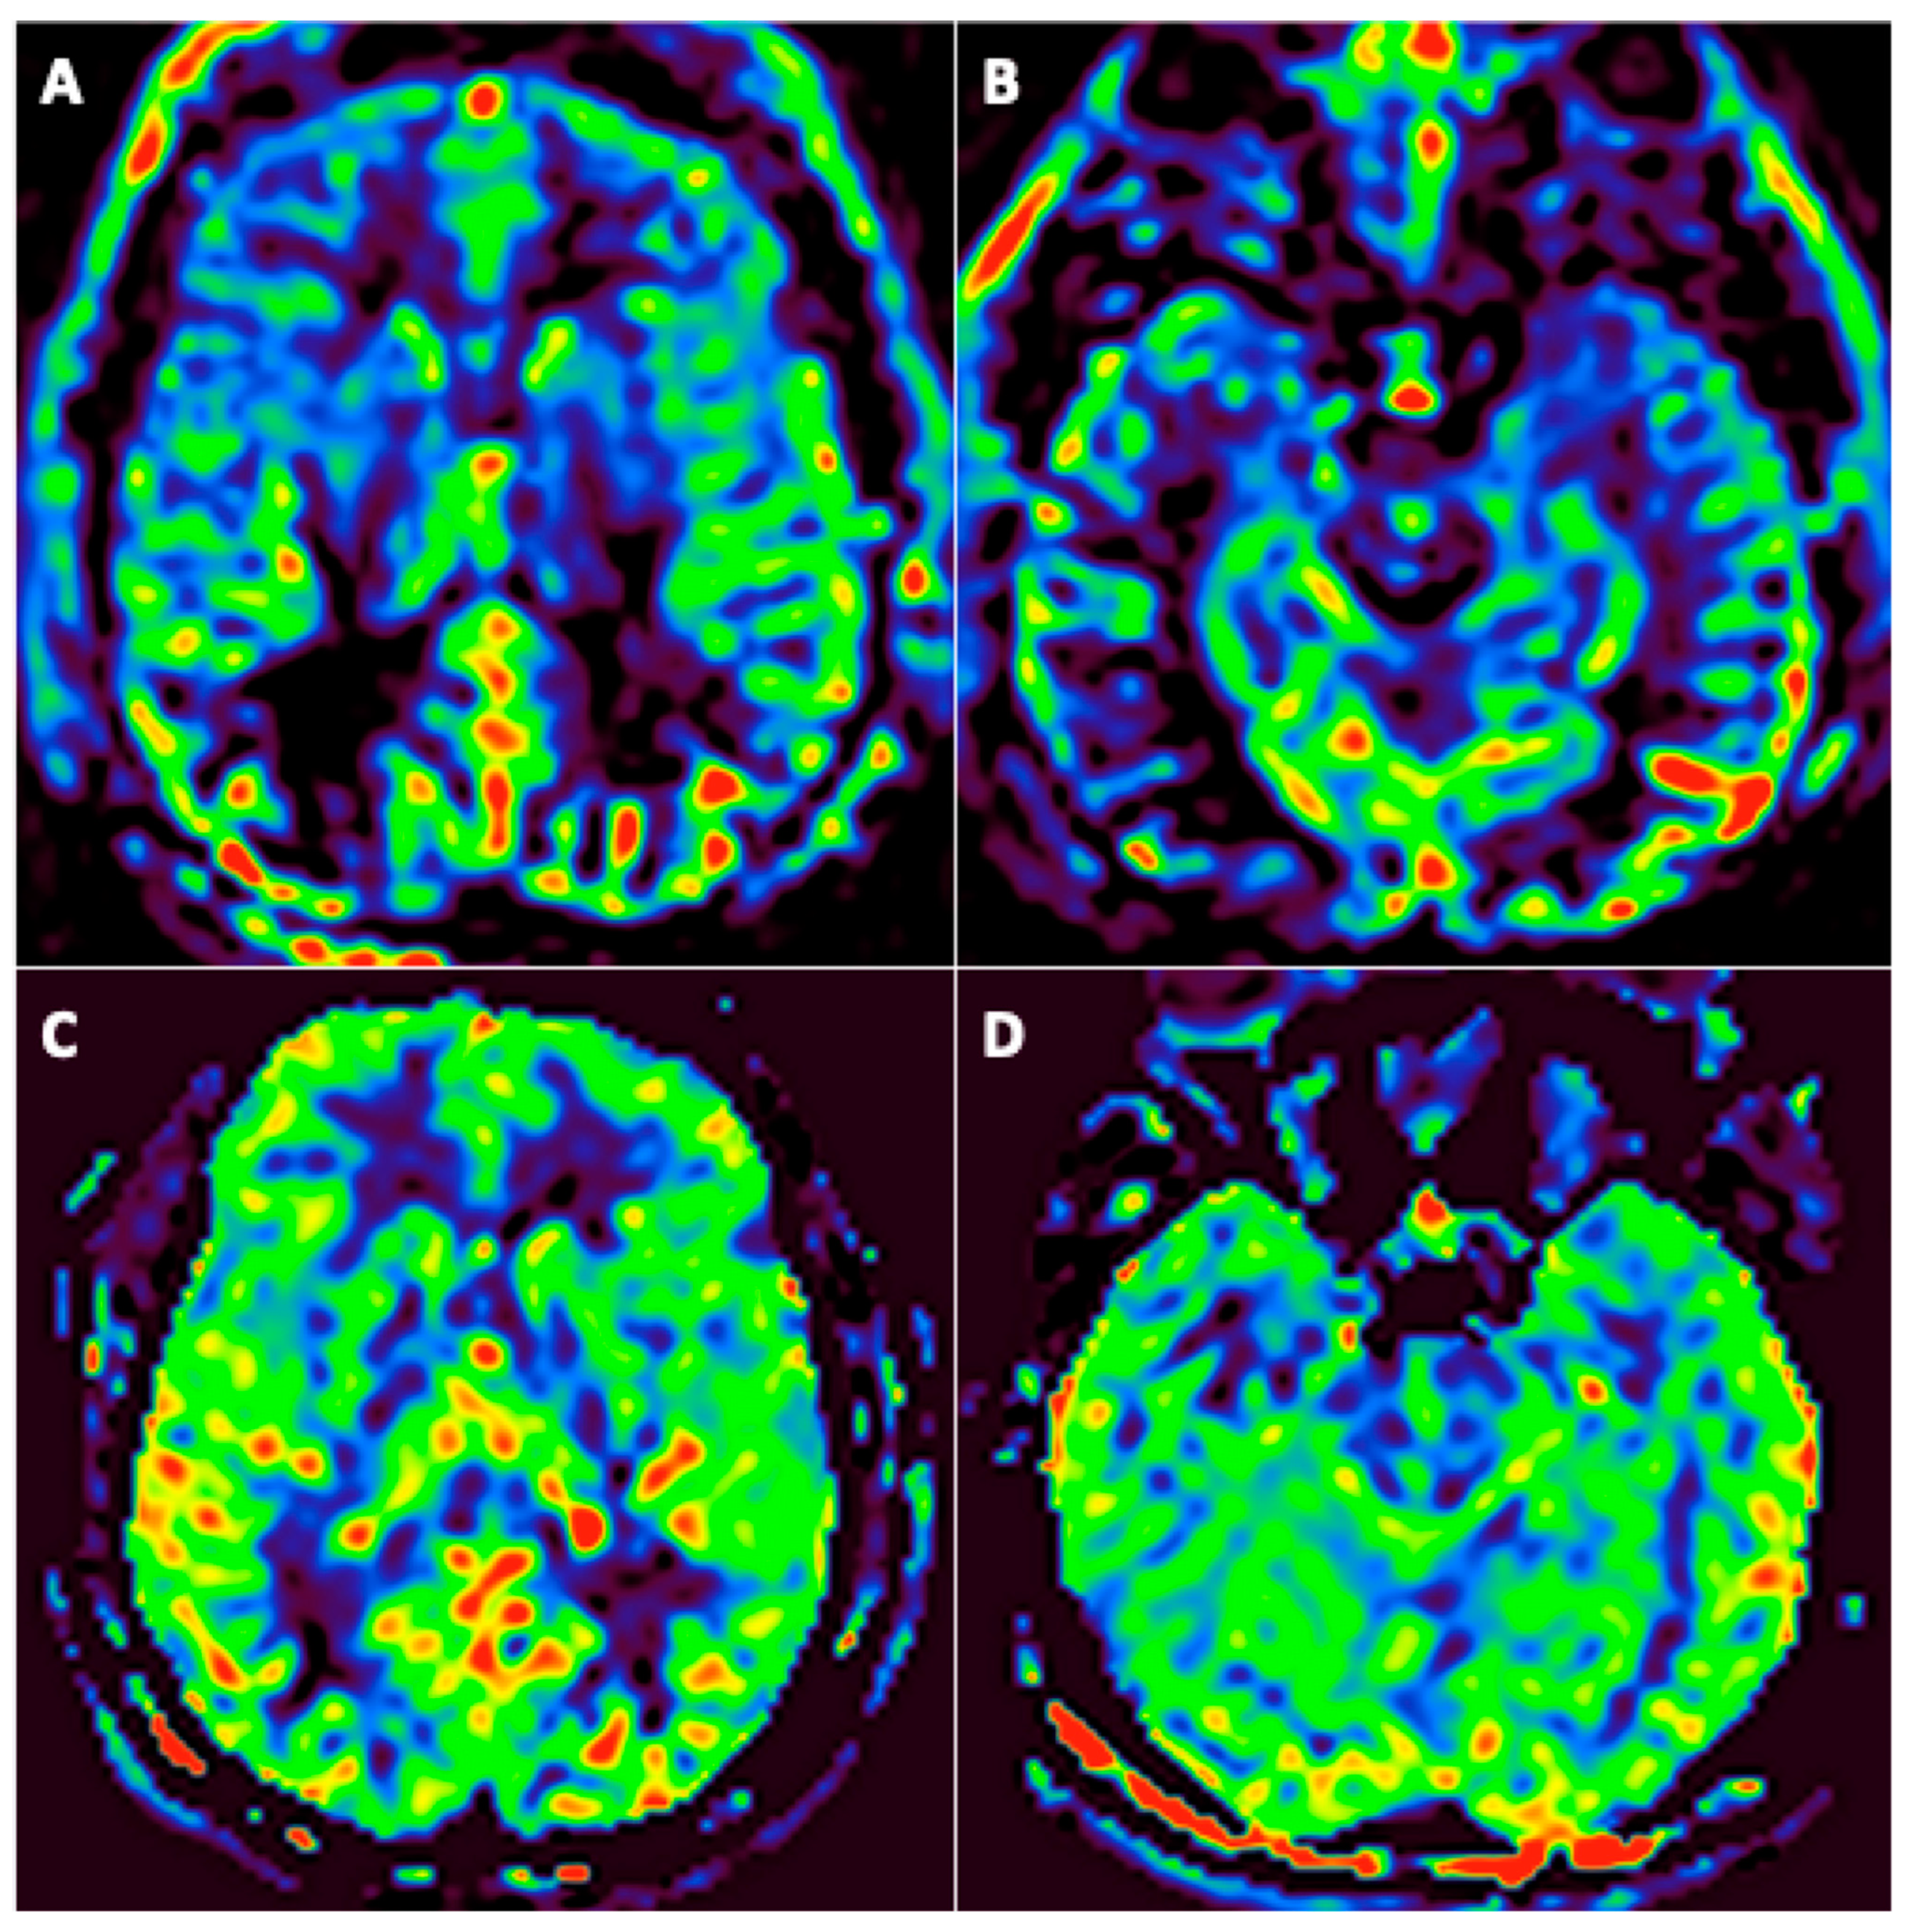

3.3. FDG-PET/CT Findings

- One patient had PET in the acute phase;

- Twenty-three patients had PET at three months (among them, 12 underwent a second PET at six months);

- One patient underwent PET at six months.

| #2 | NR | Colliculus’s hypermetabolism; Left medial temporal hypometabolism | Unchanged |

| #3 | NR | Colliculus’s hypermetabolism; Bilateral temporal polar and insular lobes (L > R) hypometabolism | Unchanged |

| #4 | NR | Colliculus’s hypermetabolism; bilateral temporo-insular and right centro-opercular region hypometabolism | Colliculus’s hypermetabolism; Improvement of hypometabolism |

| #5 | Colliculus’s hypermetabolism; Left medial temporal hypometabolism | Colliculus’s hypermetabolism; Left medial temporal hypometabolism | Regression of colliculus’s hypermetabolism; Stability of left medial temporal hypometabolism |

| #10 | NR | Bilateral temporo-insular lobes and middle cerebral artery territories hypometabolism (R > L) | Bilateral medial temporal hypometabolism |

| #11 | NR | Bilateral temporo-insular and parietal lobes hypometabolism | NR |

| #12 | NR | Left medial temporal hypometabolism | NR |

| #13 | NR | Bilateral temporo insular hypometabolism | NR |

| #14 | NR | Left medial temporal hypometabolism | Unchanged |

| #15 | NR | Bilateral temporo insular hypometabolism | NR |

| #16 | NR | Colliculus’s hypermetabolism; Bilateral temporo insular hypometabolism (L > R) | Left medial temporal hypometabolism |

| #17 | NR | Colliculus’s hypermetabolism; Medial temporal and right thalamus hypometabolism | NR |

| #18 | NR | Colliculus’s hypermetabolism | No abnormalities |

| #19 | NR | Bilateral temporal hypometabolism | NR |

| #20 | NR | Colliculus’s hypermetabolism | No abnormalities |

| #21 | NR | Left medial temporal hypometabolism | Unchanged |

| #22 | NR | Colliculus’s hypermetabolism; Bilateral temporal hypometabolism | Unchanged |

| #23 | NR | Colliculus’s hypermetabolism; Bilateral temporal hypometabolism | NR |

| #24 | NR | No abnormalities | No abnormalities |

| #26 | NR | Left medial temporal hypometabolism | NR |

| #27 | NR | Colliculus’s hypermetabolism; Bilateral temporal hypometabolism bitemporal | NR |

| #28 | NR | Left colliculus hypermetabolism;^1Right fronto-temporo-insular and left thalamus hypometabolism | NR |

| #29 | NR | Colliculus’s hypermetabolism; Bilateral parietal and temporal hypometabolism | NR |